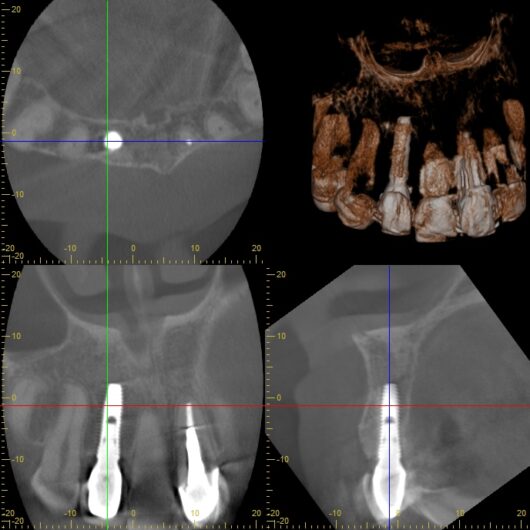

初診時レントゲン、CT

膿がおおきい

- デンタルレントゲン撮影

- CT撮影

検査の結果、インプラント周囲の骨の状態、インプラント体の位置、周囲組織の状態など、すべてにおいて問題は認められませんでした。これは、8年間適切にメインテナンスを継続してきた成果と言えるでしょう。